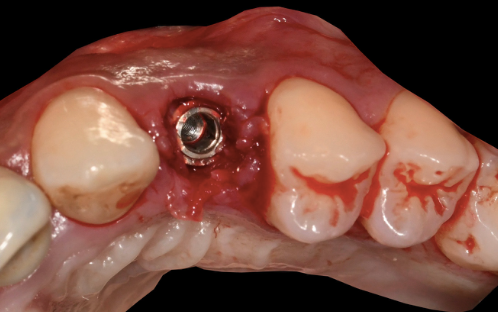

A Thommen ELEMENT RC implant (4.0 mm diameter, 11 mm length) with Inicell superhydrophilic surface was placed. The final 3D position matched the pre-operative plan exactly.

Post-placement view confirming the implant position matches the 3D plan exactly

Plan vs reality The three-dimensional implant position is identical to the pre-operative 3D plan. This is the precision that guided surgery delivers.